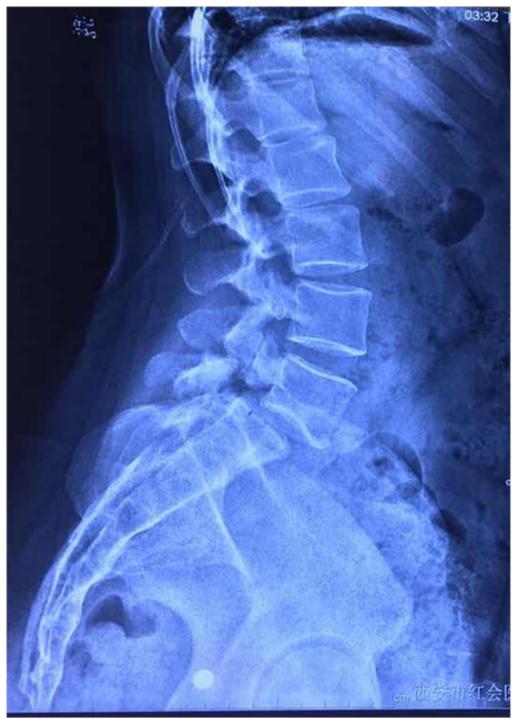

影像资料

从影像资料可以看到腰5峡部裂造成腰5骶1滑脱,滑脱有Ⅰ度。患者双侧峡部裂,也就是是由于腰部突然受力等原因导致左右两侧的椎弓峡部都断裂,但是患者只有三十多岁,比较年轻,肌肉力量比较强,避免断裂后继续向前滑移。

临床上,患者在做影像检查的时候会在站位和坐位出现明显的不同。比如这位患者核磁和CT是躺下来拍的,侧位平片是站立时拍的或卧位(但是时间较短)明显可以看到侧位平片显示的滑脱更严重。那么,腰椎滑脱该怎么判断已经发展到几度了呢?一般来说,患者在出现症状以后到医院做检查,此时如果做站立位腰椎侧位平片,可以明确滑脱的程度。